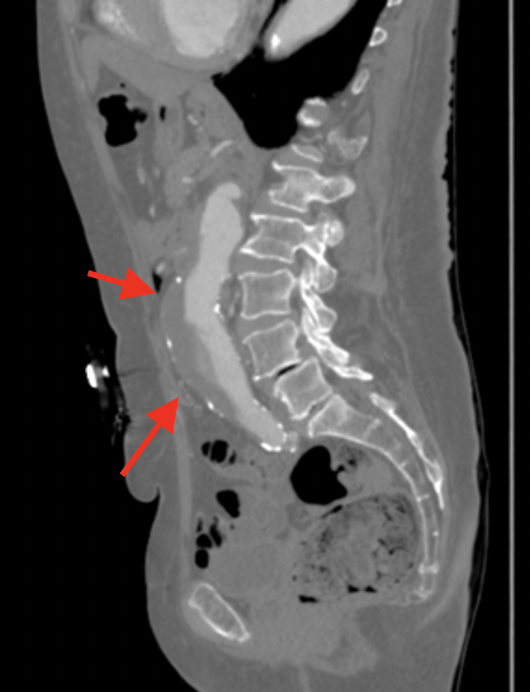

For those symptomatic who are hemodynamically stable, but with potential for other causes of abdominal pain, back pain, or flank pain, abdominal CT with contrast is the test of choice. CT can show obvious signs of rupture including retroperitoneal hematoma, and contrast extravasation. See pic to to the right.

CT might also detect “unstable” signs of impending rupture such as a crescent sign of layering hematoma in the aorta, breaks in the aortic wall calcification, and aortic blebs that emerge from the aortic surface.16